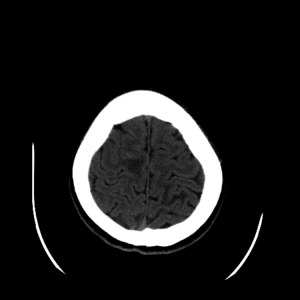

Case #3

Free